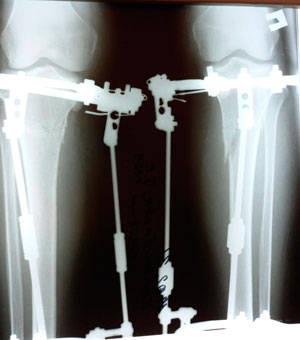

на фиксации

Вложения

image-20-02-21-12-29-2.jpg

image-20-02-21-12-29-5.jpg

image-20-02-21-12-29-4.jpg